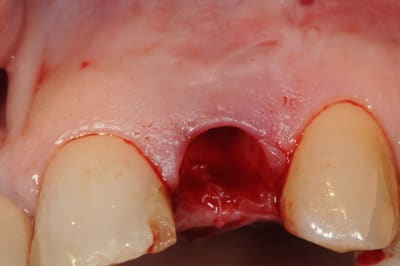

un autre cas:

bon, je triche un peu parce qu'il y a quand même implantation. on fera comme si je n'avais pas mis la photo avec l'implant en place (trop honnête moi!).

1-2: extraction la plus précautionneuse possible avec périotome..c'est long...

3-4: l’objet de toute les souffrances de mon patient. avec un gros steak de pus au bout. beuurrk!

5: curetage aussi soigneux que possible

6: alvéole propre comme un sou neuf!